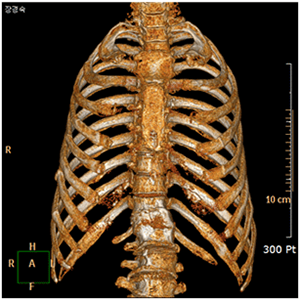

늑골 골정의 3D-CT